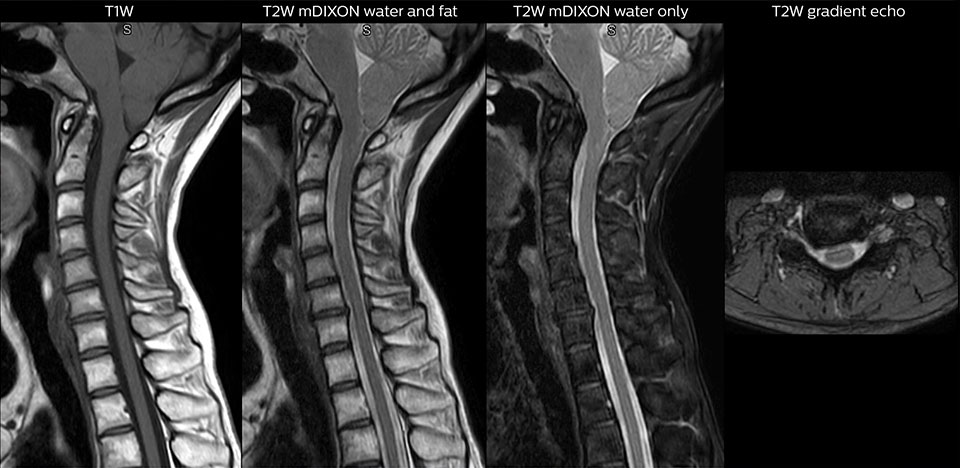

“We use mDIXON TSE extensively in our spine imaging in the emergency room,” says Dr. Karis. “It’s particularly nice in that it is very robust with regard to susceptibility type of problems that would come up with traditional spectral fat-saturated images; these problems are essentially eliminated with the mDIXON technique. In our ED environment it’s really nice to have the fat-free imaging that goes along with the mDIXON technique.

“For the thoracic and cervical spine routine non-contrast exam, for example, we perform one mDIXON T2 TSE sequence, which provides us with two outputs: the fat-and-water-together T2-weighted images, as well as the water-only sagittal T2-weighted images. And then we also perform an axial gradient echo exam.”

Routine cervical spine exam. Chiari 1 malformation with low-lying cerebellar tonsils and some degenerative cervical thrombolytic change in a patient with a headache that was worse with neck flexion.